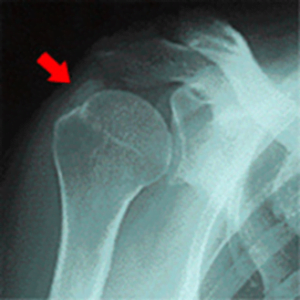

肩 脱臼 肩の脱臼・亜脱臼 「肩が抜けてしまった」という表現をして、病院にいらっしゃる方がいます。 医学的には、「肩関節脱臼」と言われるものです。 肩関節脱臼とは? 日本整形外科学会HPから掲載 肩関節は、肩甲骨と上腕骨の2つの骨で成り立っています。 何かの原因で、上腕骨が肩甲骨の関節から逸脱し、正常な位置に無い場合を脱臼していると言います。 ...

肩 【公式】柏で「石灰沈着性腱板炎」専門の整体 石灰沈着性腱板炎とは? 朝、起きたら腕が痛くて、自由に動かせないといったことがありませんか? なぜ、このようなことが起こるのでしょうか? 肩の痛みの原因 日本整形外科学会のHPより引用 何らかの炎症が肩に生じていることが考えられます。 その炎症の原因の一つに、「石灰沈着性腱板炎」があります。 レントゲンを撮ると肩の部分...